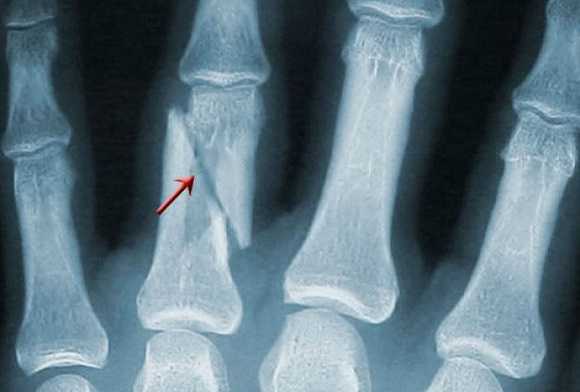

Снимки 11—V пальцев в прямой ладонной проекции .

Исследуемый палец укладывают ладонной поверхностью на неперекрытую половину кассеты размером 13X18 см. Пучок рентгеновского излучения направляют на проекцию проксимального межфалангового сустава (рис. 378).

На рентгенограмме видны фаланги и может быть частично видна I пястная кость, их медиальные и латеральные края, щели межфаланговых суставов (рис. 379).

Снимки 11—V пальцев в боковой проекции. Исследуемый палец укладывают на свободную половину кассеты размером 13X18 см ульнарным или радиальным краем (как удобнее для данного пальца).

Остальные пальцы отгибают, для фиксации удерживают противоположной кистью.

Пучок рентгеновского излучения направляют отвесно на проекцию проксимального межфалангового сустава (рис. 380).

На рентгенограмме видны фаланги пальцев, их тыльная и ладонная поверхности, бугристость дистальной фаланги, рентгеновские суставные щели межфаланговых суставов (рис.381).